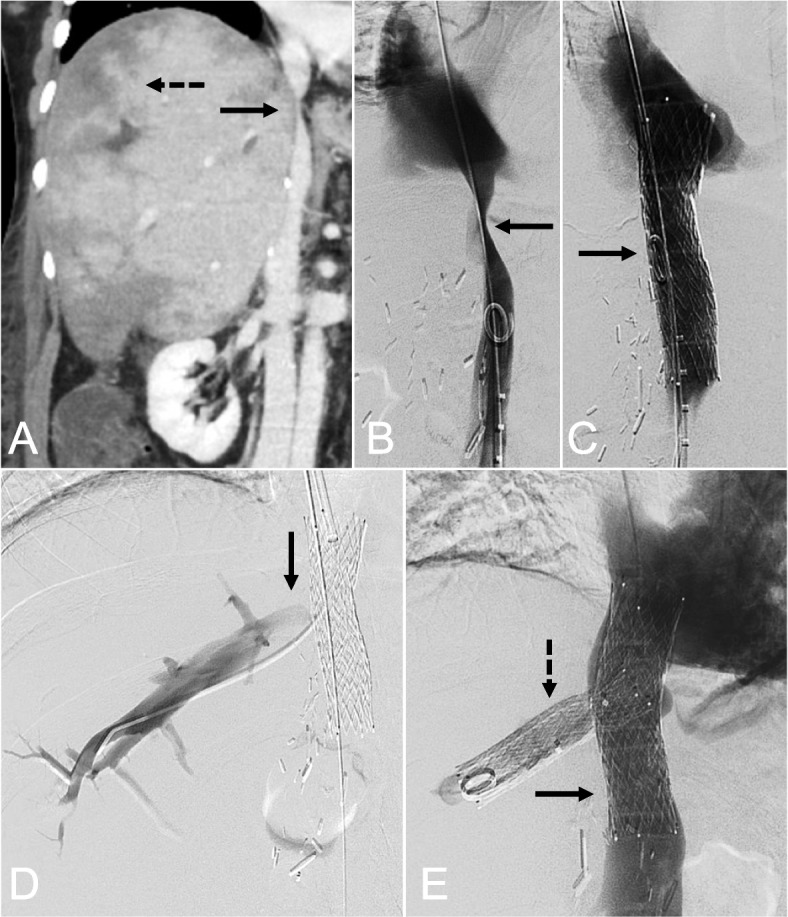

Bifurcated hepatocaval stent reconstruction for treatment of hepatic venous outflow obstruction in orthotopic liver transplantation.

原位肝移植中肝静脉流出梗阻的肝腔分岔支架重建。